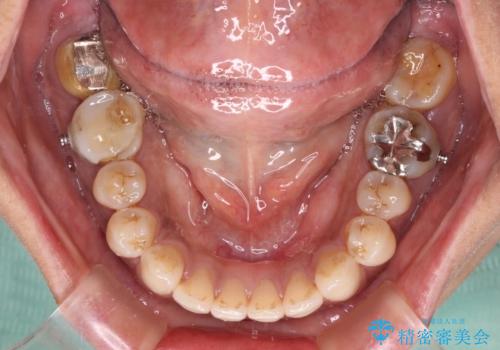

極端な上下前歯の開咬を改善 オープンバイトのインビザライン矯正

- 上下前歯の隙間を気にして来院された患者様です。

開咬の治療は、前歯を閉じるように動かすとともに、上下臼歯を圧下(骨内にめり込ませる)させることで進めて行きます。

インビザラインは臼歯の圧下を効果的に行えるため、インビザラインを用いて矯正治療を行うこととしました。

また、下顎大臼歯に根管治療が必要な歯があるため、矯正治療と並行して治療を行い、矯正後に補綴治療することとしました。